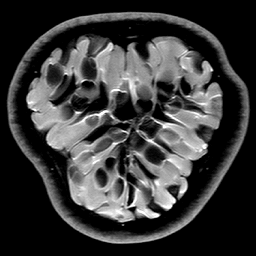

|

|

|

| Original image | Gauss. to DB4, err=31.54% | Gauss. to Flip DB4, err=31.51% |

|

|

|

| Subsampling pattern | DFT to DB4, err=10.96% | DFT to Flipped DB4, err=99.3% |

Since it will become important later, we now describe a quick and simple test, which we call the flip test, to investigate the presence or absence of an RIP. Success of this test suggests the existence of an RIP and failure demonstrates its lack.

Let be a sensing matrix, an image and a sparsifying transformation. Recall that sparsity of the vector is unaffected by permutations. Thus, let us define the flipped vector

and using this, we construct the flipped image Note that, by construction, we have . Now suppose we perform the usual compressed sensing reconstruction (1) on both and , giving approximations and . We now wish to reverse the flipping operation. Thus, we compute which gives a second approximation to the original image .

This test provides a simple way to investigate whether or not the RIP holds. To see why, suppose that satisfies the RIP. Then by construction, we have that

Hence both and should recover equally well. In the top row of Figure 1 we present the result of the flip test for a Gaussian random matrix. As is evident, the reconstructions and are comparable, thus indicating the RIP.

Having considered type II problems, let us now examine the flip test for a type I problem. As discussed, in applications such as MRI, X-ray CT, radio interferometry, etc, the matrix is imposed by the physical sensing device and arises from subsampling the rows of the DFT matrix .111In actual fact, the sensing device takes measurements of the continuous Fourier transform of a function . As discussed in BAACHGSCS ; BAGSAIEP , modelling continuous Fourier measurements as discrete Fourier measurements can lead to inferior reconstructions, and worse, inverse crimes. To avoid this, one must consider an infinite-dimensional compressed sensing approach, as in (2). See AHPRBreaking ; BAGSAIEP for details, as well as PruessmannUnserMRIFast for implementation in MRI. However, for simplicity, we shall continue to work with the finite-dimensional model in the remainder of this paper. Whilst one often has some freedom to choose which rows to sample (corresponding to selecting particular frequencies at which to take measurements), one cannot change the matrix .

It is well known that in order to ensure a good reconstruction, one cannot subsample the DFT uniformly at random (recall that the sparsifying transform is a wavelet basis), but rather one must sample randomly according to an appropriate nonuniform density AHPRBreaking ; Candes_Romberg ; Lustig ; WangAcre . See the bottom left panel of Figure 1 for an example of a typical density. As can be seen in the next panel, by doing so one achieves a great recovery. However, the result of the flip test in the bottom right panel clearly demonstrates that the matrix does not satisfy an RIP. In particular, the ordering of the wavelet coefficients plays a crucial role in the reconstruction quality. To explain this, and in particular, the high-quality reconstruction seen in the unflipped case, one evidently requires a new analytical framework.

Note that the flip test in Figure 1 also highlights another important phenomenon: namely, the effectiveness of the subsampling strategy depends on the sparsity structure of the image. In particular, two images with the same total sparsity (the original and the flipped ) result in wildly different errors when the same sampling pattern is used. Thus we conclude that there is no one optimal sampling strategy for all sparse vectors of wavelet coefficients.

Having identified a measurement matrix to exploit structured sparsity, let us demonstrate its effectiveness. In Figure 5 we compare these measurements with the case of random Bernoulli measurements (this choice was made over random Gaussian measurements because of storage issues). As is evident, at all resolutions we see a significant advantage, since the former strategy exploits the structured sparsity. Note that for both approaches, the reconstruction quality is resolution dependent: the error decreases as the resolution increases, due to the increasing sparsity of wavelet coefficients at higher resolutions. However, because the Fourier/wavelets matrix is asymptotically incoherent (see also Section 4.1), it exploits the inherent asymptotic sparsity structure (6) of the wavelet coefficients as the resolution increases, and thus gives successively greater improvements over random Bernoulli measurements.

Recall that in type I problems such as MRI, we are constrained by the physics of the device to take Fourier measurements. A rather strange conclusion of Figure 5 is the following: compressed sensing actually works better for MRI with the intrinsic measurements, than if one were able to take optimal (in the sense of the standard sparsity-based theory) random (sub)Gaussian measurements. This has practical consequences. In MRI there is actually a little flexibility to design measurements, based on specifying appropriate pulses. By doing this, a number of approaches HaldarRandomEncoding ; ToeplitzMRI ; VanderEtAlSpreadSpectrum ; SebertRandomMRI ; WongMRI have been proposed to make MRI measurements closer to uniformly incoherent with wavelets (i.e. similar to random Gaussians). On the other hand, Figure 5 suggests that one can obtain great results in practice by appropriately subampling the unmodified Fourier operator.